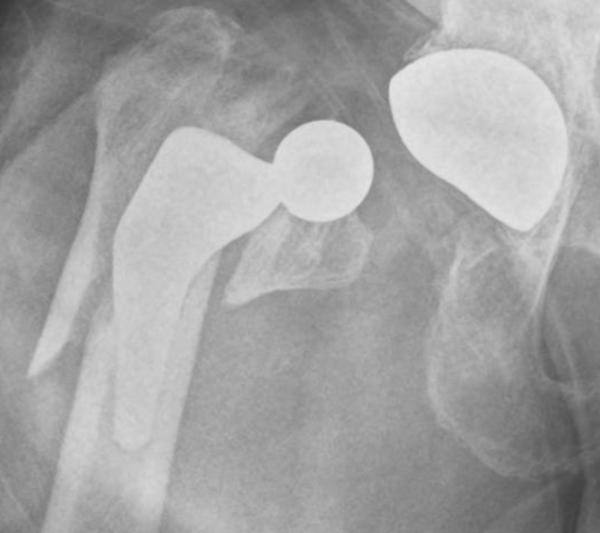

Fracture sur Prothèse